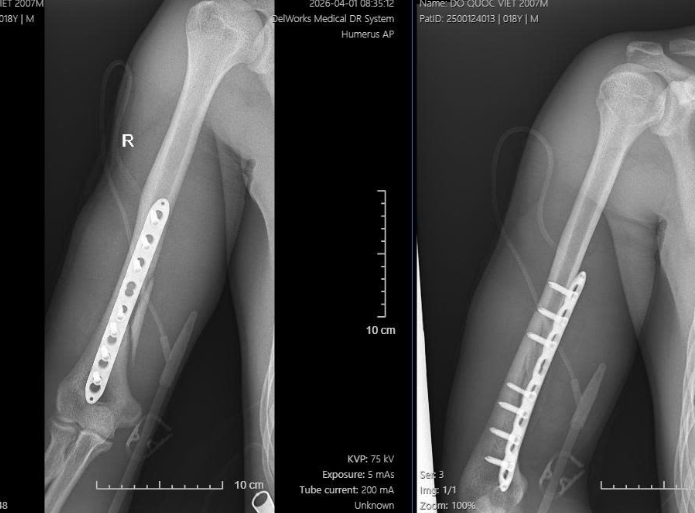

Sau khi hội chẩn, bệnh nhân được chỉ định phẫu thuật kết hợp xương cánh tay bằng nẹp vít. Ca mổ được thực hiện sớm, giúp kiểm soát tốt ổ gãy, đảm bảo độ vững chắc và tạo điều kiện thuận lợi cho quá trình phục hồi chức năng sau mổ.

Hình 3. Phim XQ sau mổ, ổ gãy phức tạp được kiểm soát tốt, đủ vững chắc, trục chi và chiều dài chi đạt, tạo điều kiện tốt cho phục hồi chức năng sau mổ.